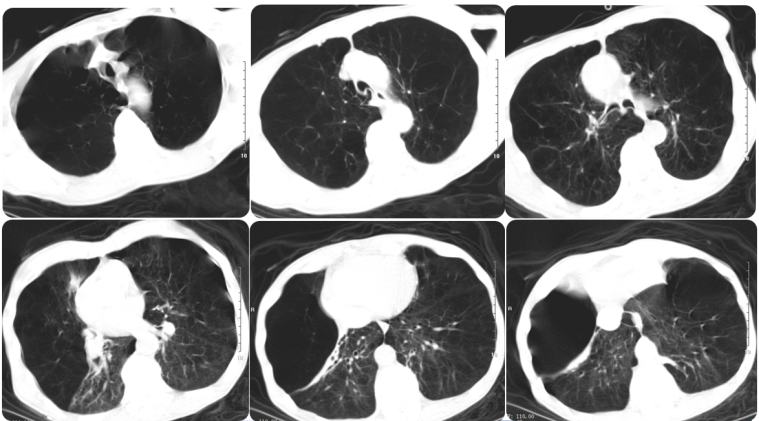

患者术后血气分析(鼻导管2 L/min):pH 7.425,PaO2 61.8 mmHg,PaCO2 46.8 mmHg,HCO3- 30.0 mmol/L。术后当天脱机,术后1天离床站立活动,三凹征明显改善。术后5天复查胸部CT可见右上肺大疱体积明显减小,但右上肺出现肺不张图2

图片

图2  患者肺减容术后5天胸部CT

EBV术后出现肺不张是必需的吗?或者没有肺不张,只是大疱减小就可以?在一项10年生存率的随访研究中有19例患者进行了一代EBV手术,患者分为肺不张组和非肺不张组,结果显示肺不张组的存活率显著高于非肺不张组。